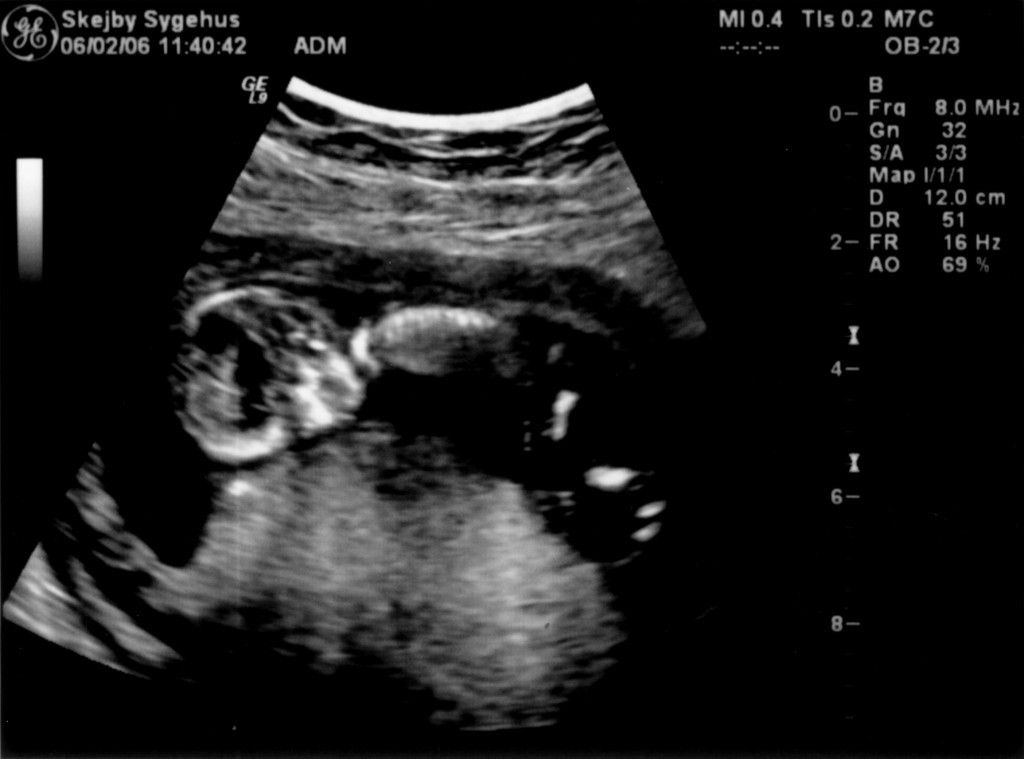

Vi har så endelig været på Skejby Sygehus, hvor specialisterne skulle vurdere babys hjerte. Konklussionen var at baby og hendes hjerte ikke fejler noget - alt er i den skønneste orden. Der blev foretaget en meget grundig skanning og billederne blev vurderet af en afdelingslæge, en overlæge samt en overlæge med mange års international erfaring i børns hjertefejl. Det var en stor lettelse at hun ikke fejler noget. Baby blev undersøgt generelt en gang til at specialisterne og alt er som det skal være. De kunne desuden konstatere, at det er en pige... Du kan se de billeder vi fik fra skanningen herunder.

Baby ligger med hovedet nederst i midten og kigger op. Hun flekser så meget i ryggen at hendes ben går helt op over hovedet. Babys hjerte med nogle målinger.